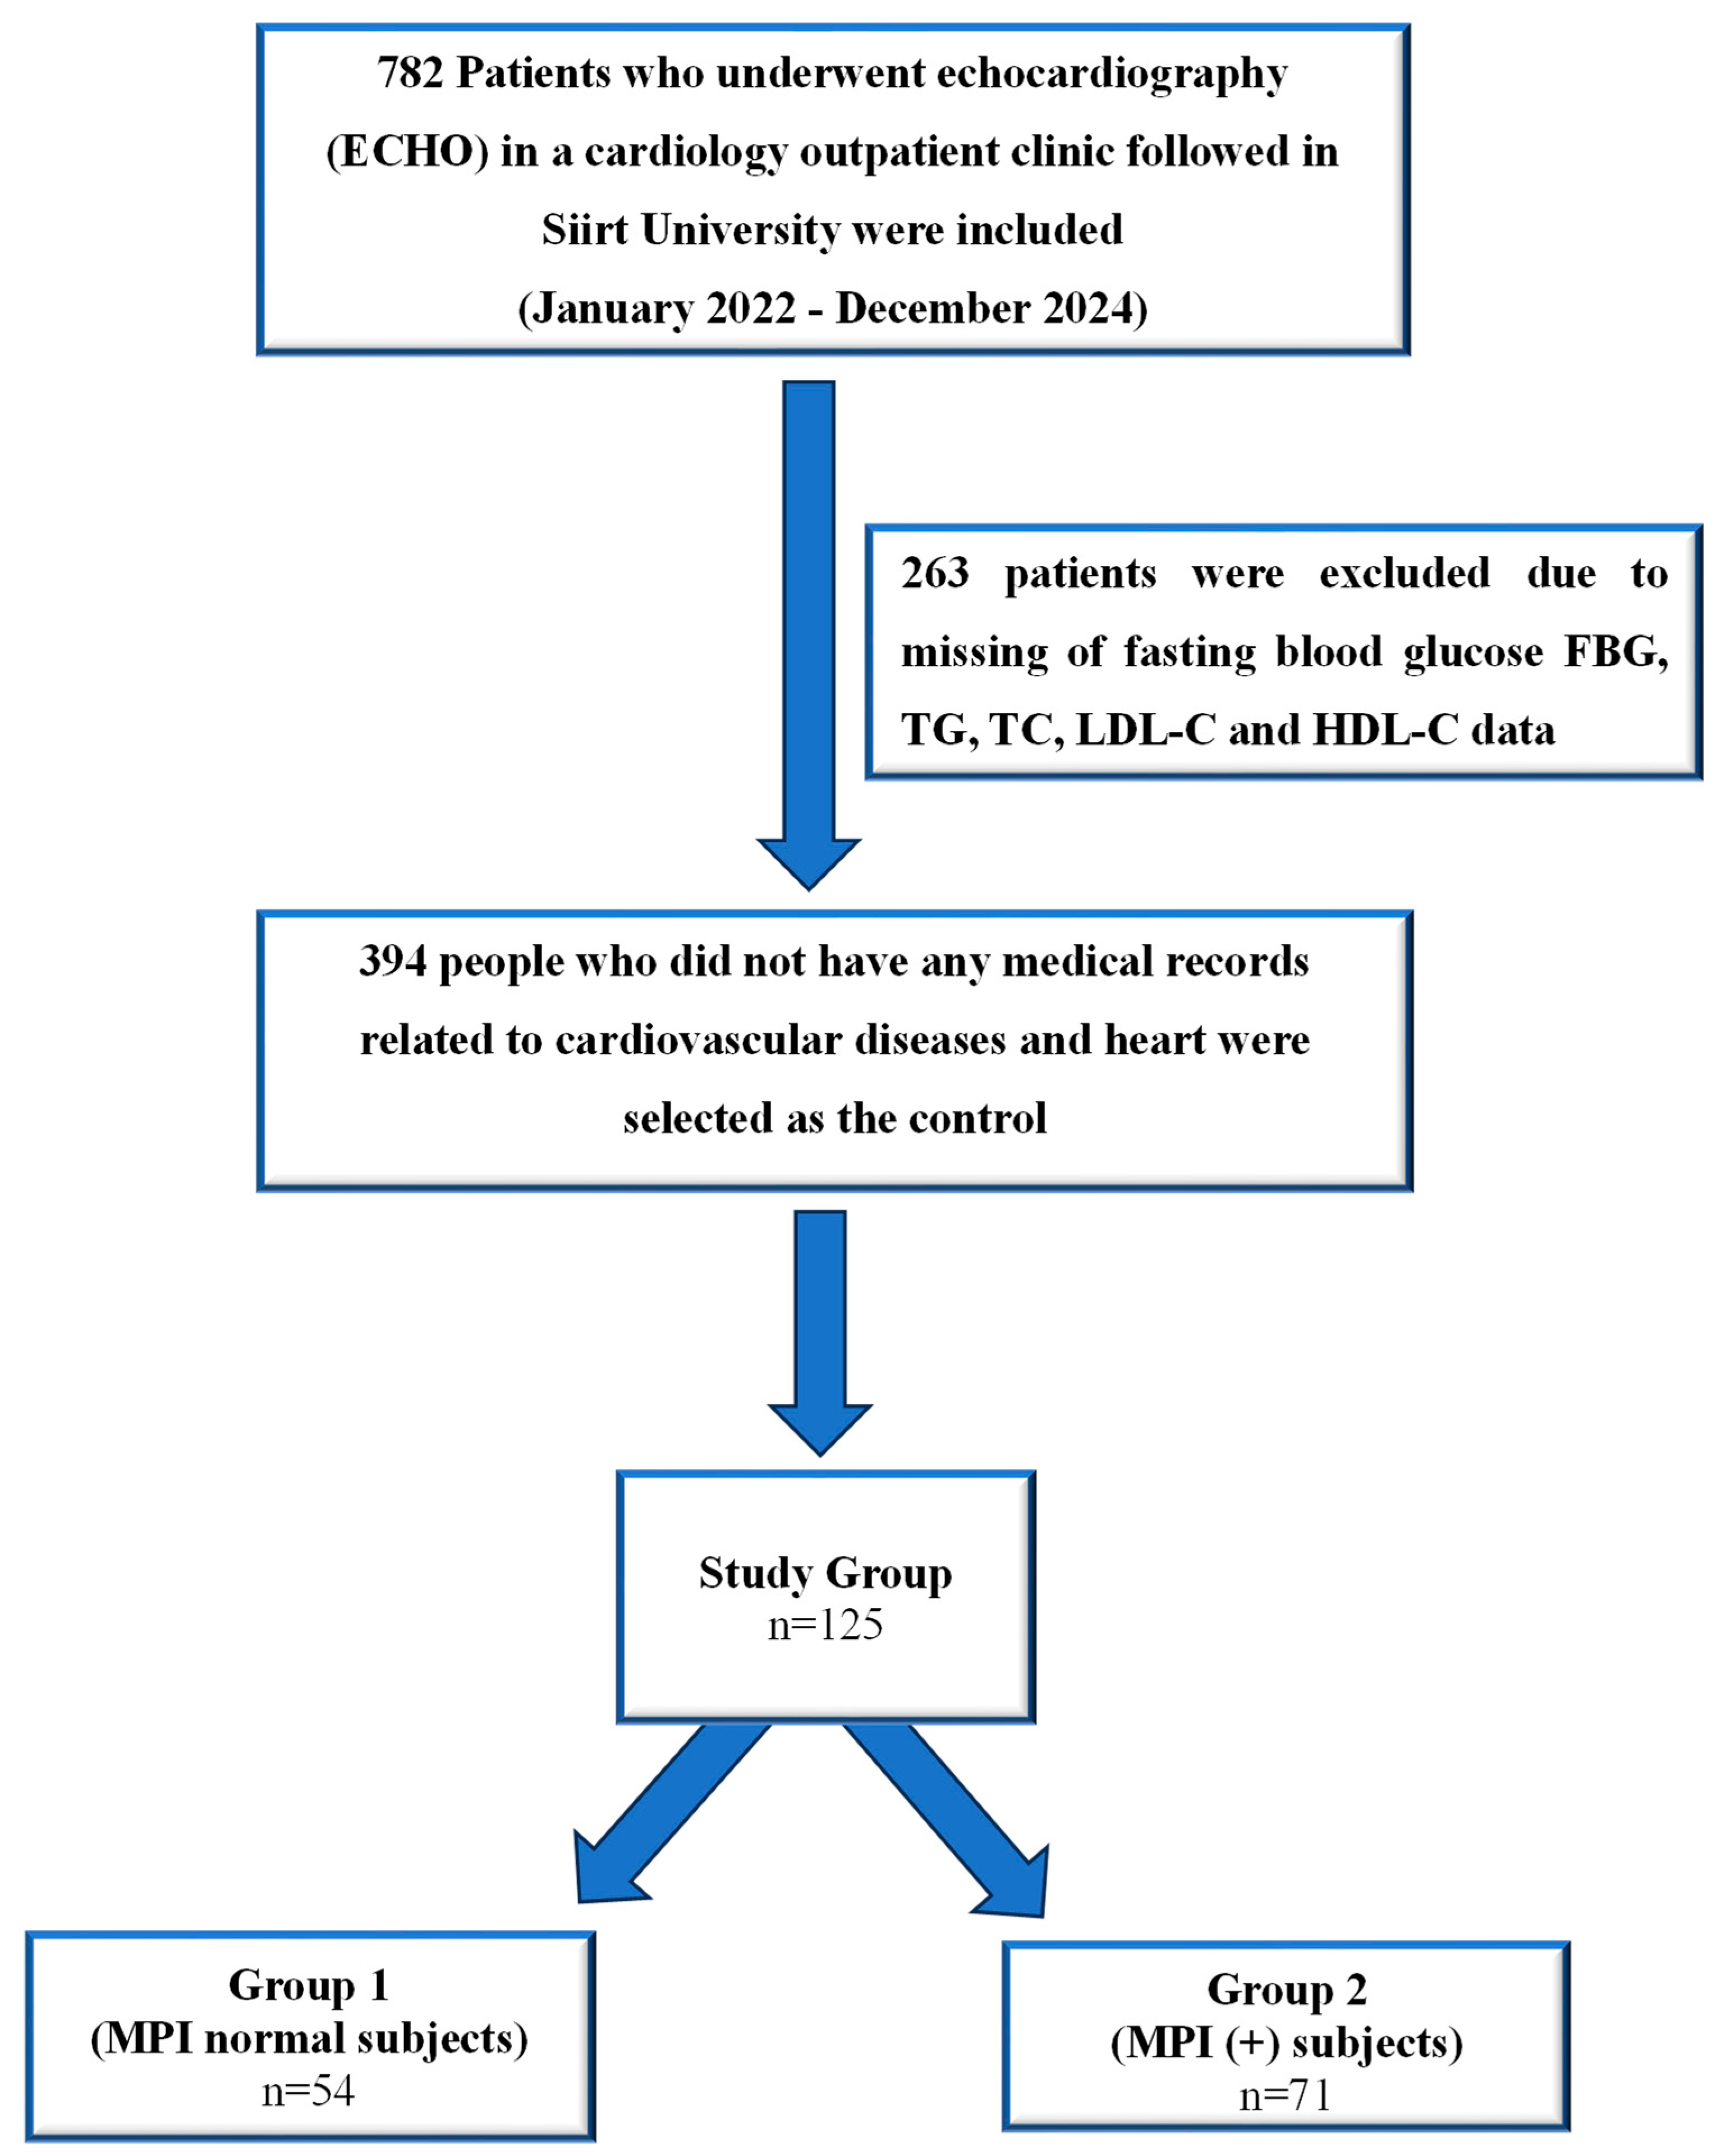

2. Materials and Method

2.2. Study Populations

2.3. The Inclusion Criteria

2.4. The Exclusion Criteria